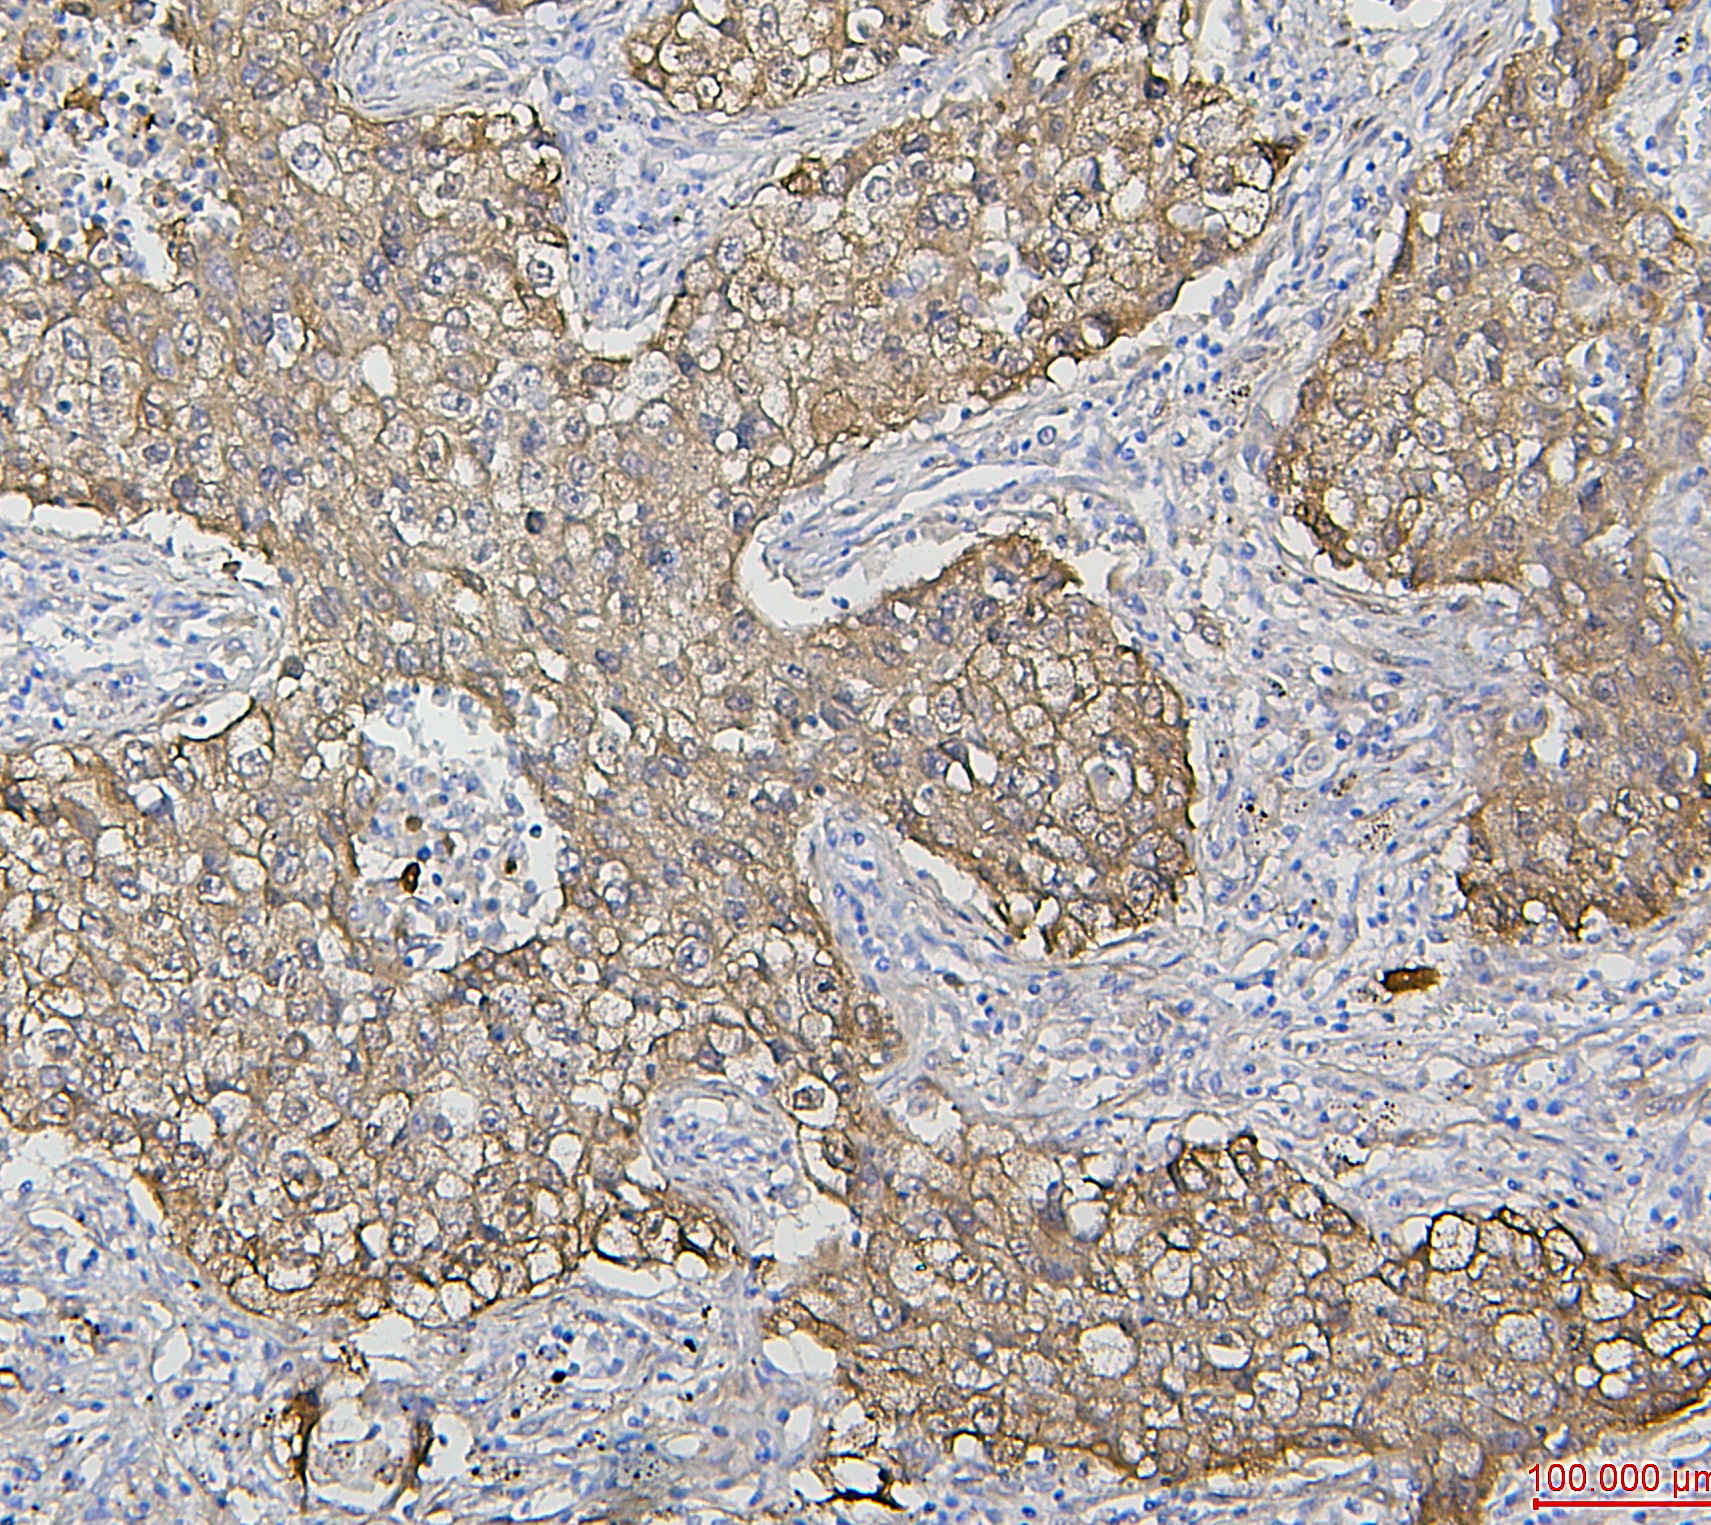

IHC analysis of HSP27/HSPB1 using anti-HSP27/HSPB1 antibody (M00676-5).

HSP27/HSPB1 was detected in a paraffin-embedded section of human lung cancer tissue. Biotinylated goat anti-mouse IgG was used as secondary antibody. The tissue section was incubated with mouse anti-HSP27/HSPB1 Antibody (M00676-5) at a dilution of 1:200 and developed using Strepavidin-Biotin-Complex (SABC) (Catalog # SA1021) with DAB (Catalog # AR1027) as the chromogen.